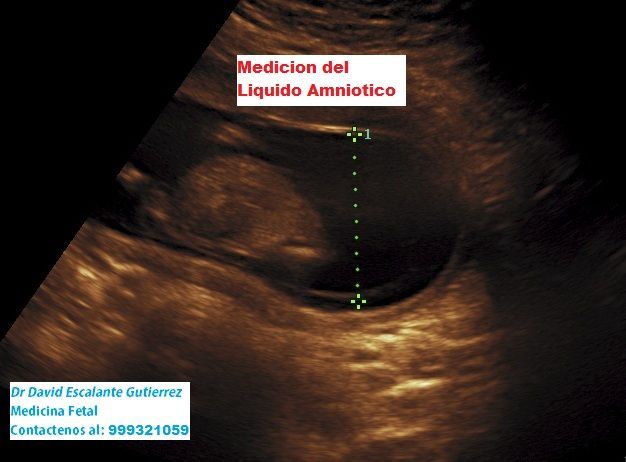

Realizamos las ecografías de viabilidad del embarazo, genética, morfológica, de bienestar fetal, ecocardiografías fetales, así como procedimientos invasivos como biopsia de vellosidades coriales y amniocentesis.